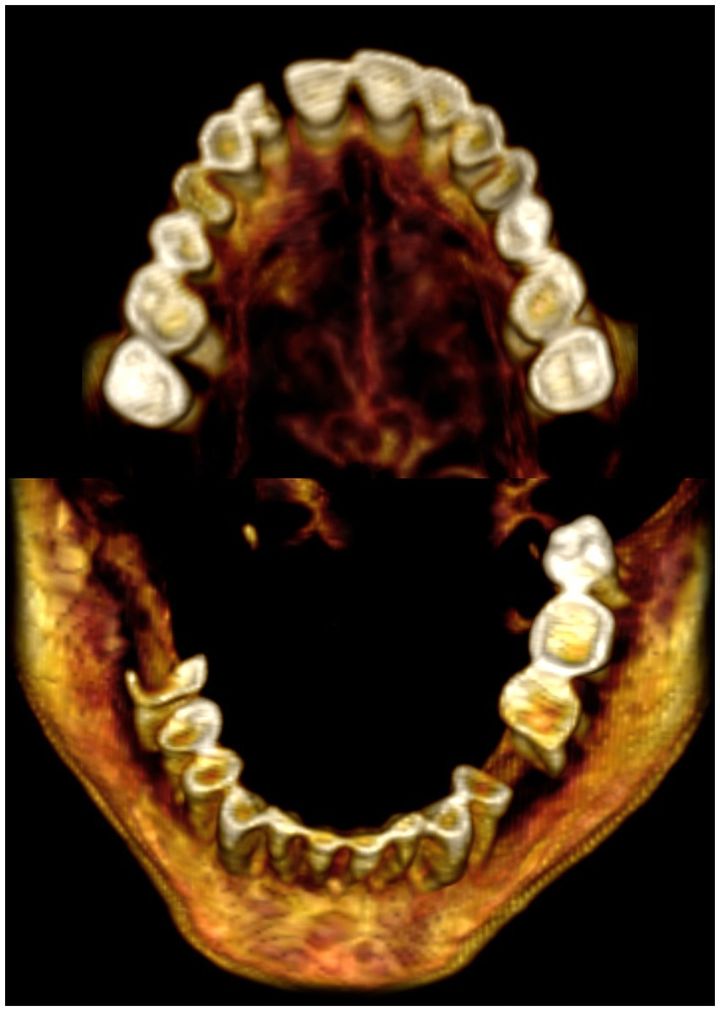

歯のスキャン画像

歯のスキャン画像 / Credit: Sahar N. Saleem et al., Frontiers in Medicine(2024)

バーチャル解剖の結果、彼女の身長は約1.54メートルで、加齢とともに変化する骨盤の関節の分析から年齢は48歳ほどであると推定されました。

また軽度の関節炎を脊椎に患っており、背骨の一部には骨がトゲのように変形して痛みを起こす「骨棘(こっきょく)」ができていることもCTスキャンで判明しています。

口内には数本ほど見当たらない歯があり、亡くなる前に抜けたと見られています。

チームは遺体にダメージを与えることなく、隅々まで調べるため、走査型電子顕微鏡、赤外分光法、X線分析などを駆使した”バーチャル解剖”を試みています。